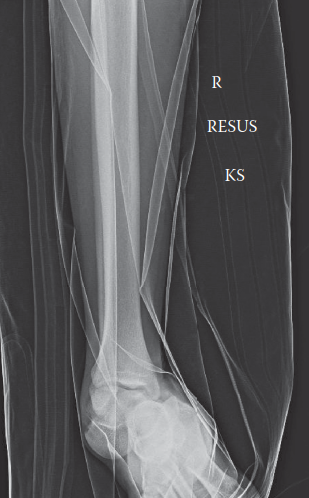

KS A 28-year-old man is brought to the emergency department after falling from a high wall late in the evenin…